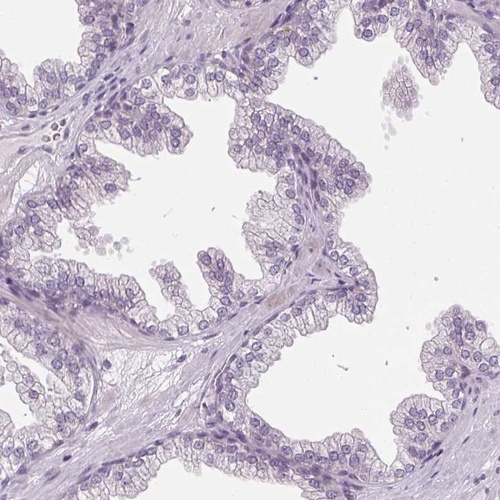

Immunohistochemistry analysis in human skeletal muscle and prostate tissues using Anti-KLHL40 antibody. Corresponding KLHL40 RNA-seq data are presented for the same tissues.